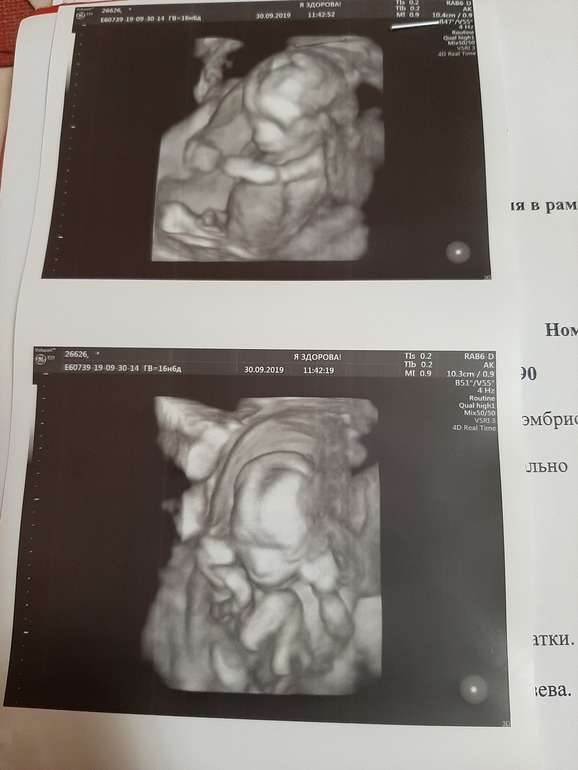

Ну какая ж страшненькая!???!!! Красотка!!! И у неё все на месте, и она на месте, пусть растёт и созревает до положенного срока и выхода в свет! ✌🏻😉

Сами вы страшненькая!😁 она просто чуть не причесанная и не выспалась, как любая девочка!🤣 Здоровья обеим!

Поздравляю с доченькой!!!Это настоящее счастье,по себе знаю❤!!!Растите здоровенькими)

Боже, какое чудо. Красоточка крохотная! Растите здоровенькими 💞